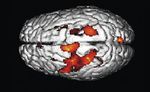

Beschreibung und Definition klinischer Merkmale („Phäno-                 Die experimentelle Auslösung von Juckreiz beim Menschen aktiviert auch

verschiedene Großhirnareale, hier in rot dargestellt. Der Nachweis gelingt

typisierung“) der untersuchten Krankheit ist, damit in den gross         mit bildgebenden Verfahren wie der Positronen-Emissions-Tomographie

angelegten Studien und aufwendigen Methoden aussagekräftige              (PET) (Darsow, Czega et al 2004).

Ergebnisse erzielt werden können. Die hohe Kunst der klinischen          The activation of different brain areas provoked by histamine mediated itch

Diagnostik ist damit wieder ins Zentrum der Wissenschaft gerückt.        induction can be visualized with modern imaging techniques like positron

emission tomography (Darsow, Czega et al 2004).